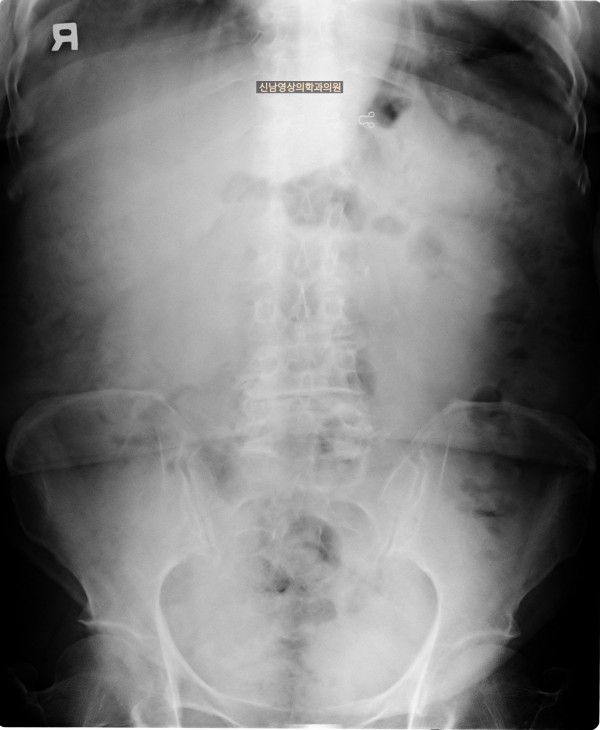

본 환자분은 변비가 지속되면서 좌하복부 통증이 있으셨던 분으로 본원에서 복부 초음파 검사를 진행하였습니다.

하행 결장 부위에서 장이 두꺼워진 소견이 보여 진행된 대장암의 가능성이 농후해보여 대학병원으로 전원해 대장내시경을 받고, 수술로 2기암으로 진단되신 케이스입니다.

복부 초음파는 대장암을 직접 진단하는 검사는 아니지만 대장암이 간이나 복막으로 전이된 경우 전이된 종양을 확인하거나 내시경 초음파를 통해 대장암의 깊이를 평가하는 데 활용할 수 있습니다.

대장암 자체를 진단하는 데는 대장 내시경, CT, 내시경 초음파 등의 검사가 더 적합하며, 전이 여부는 CT나 MRI 등으로 확인하는 것이 일반적입니다.